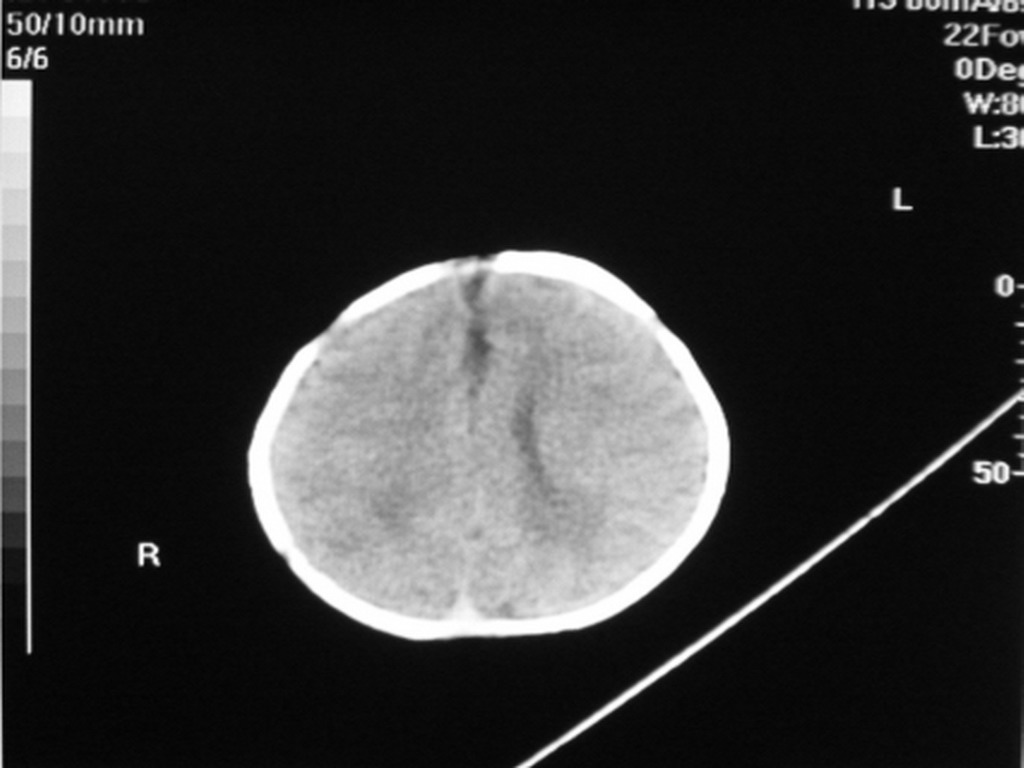

标题: PED1877:女,20余天,突发抽搐,双眼凝视。 [打印本页]

女,20余天,突发抽搐,双眼凝视。